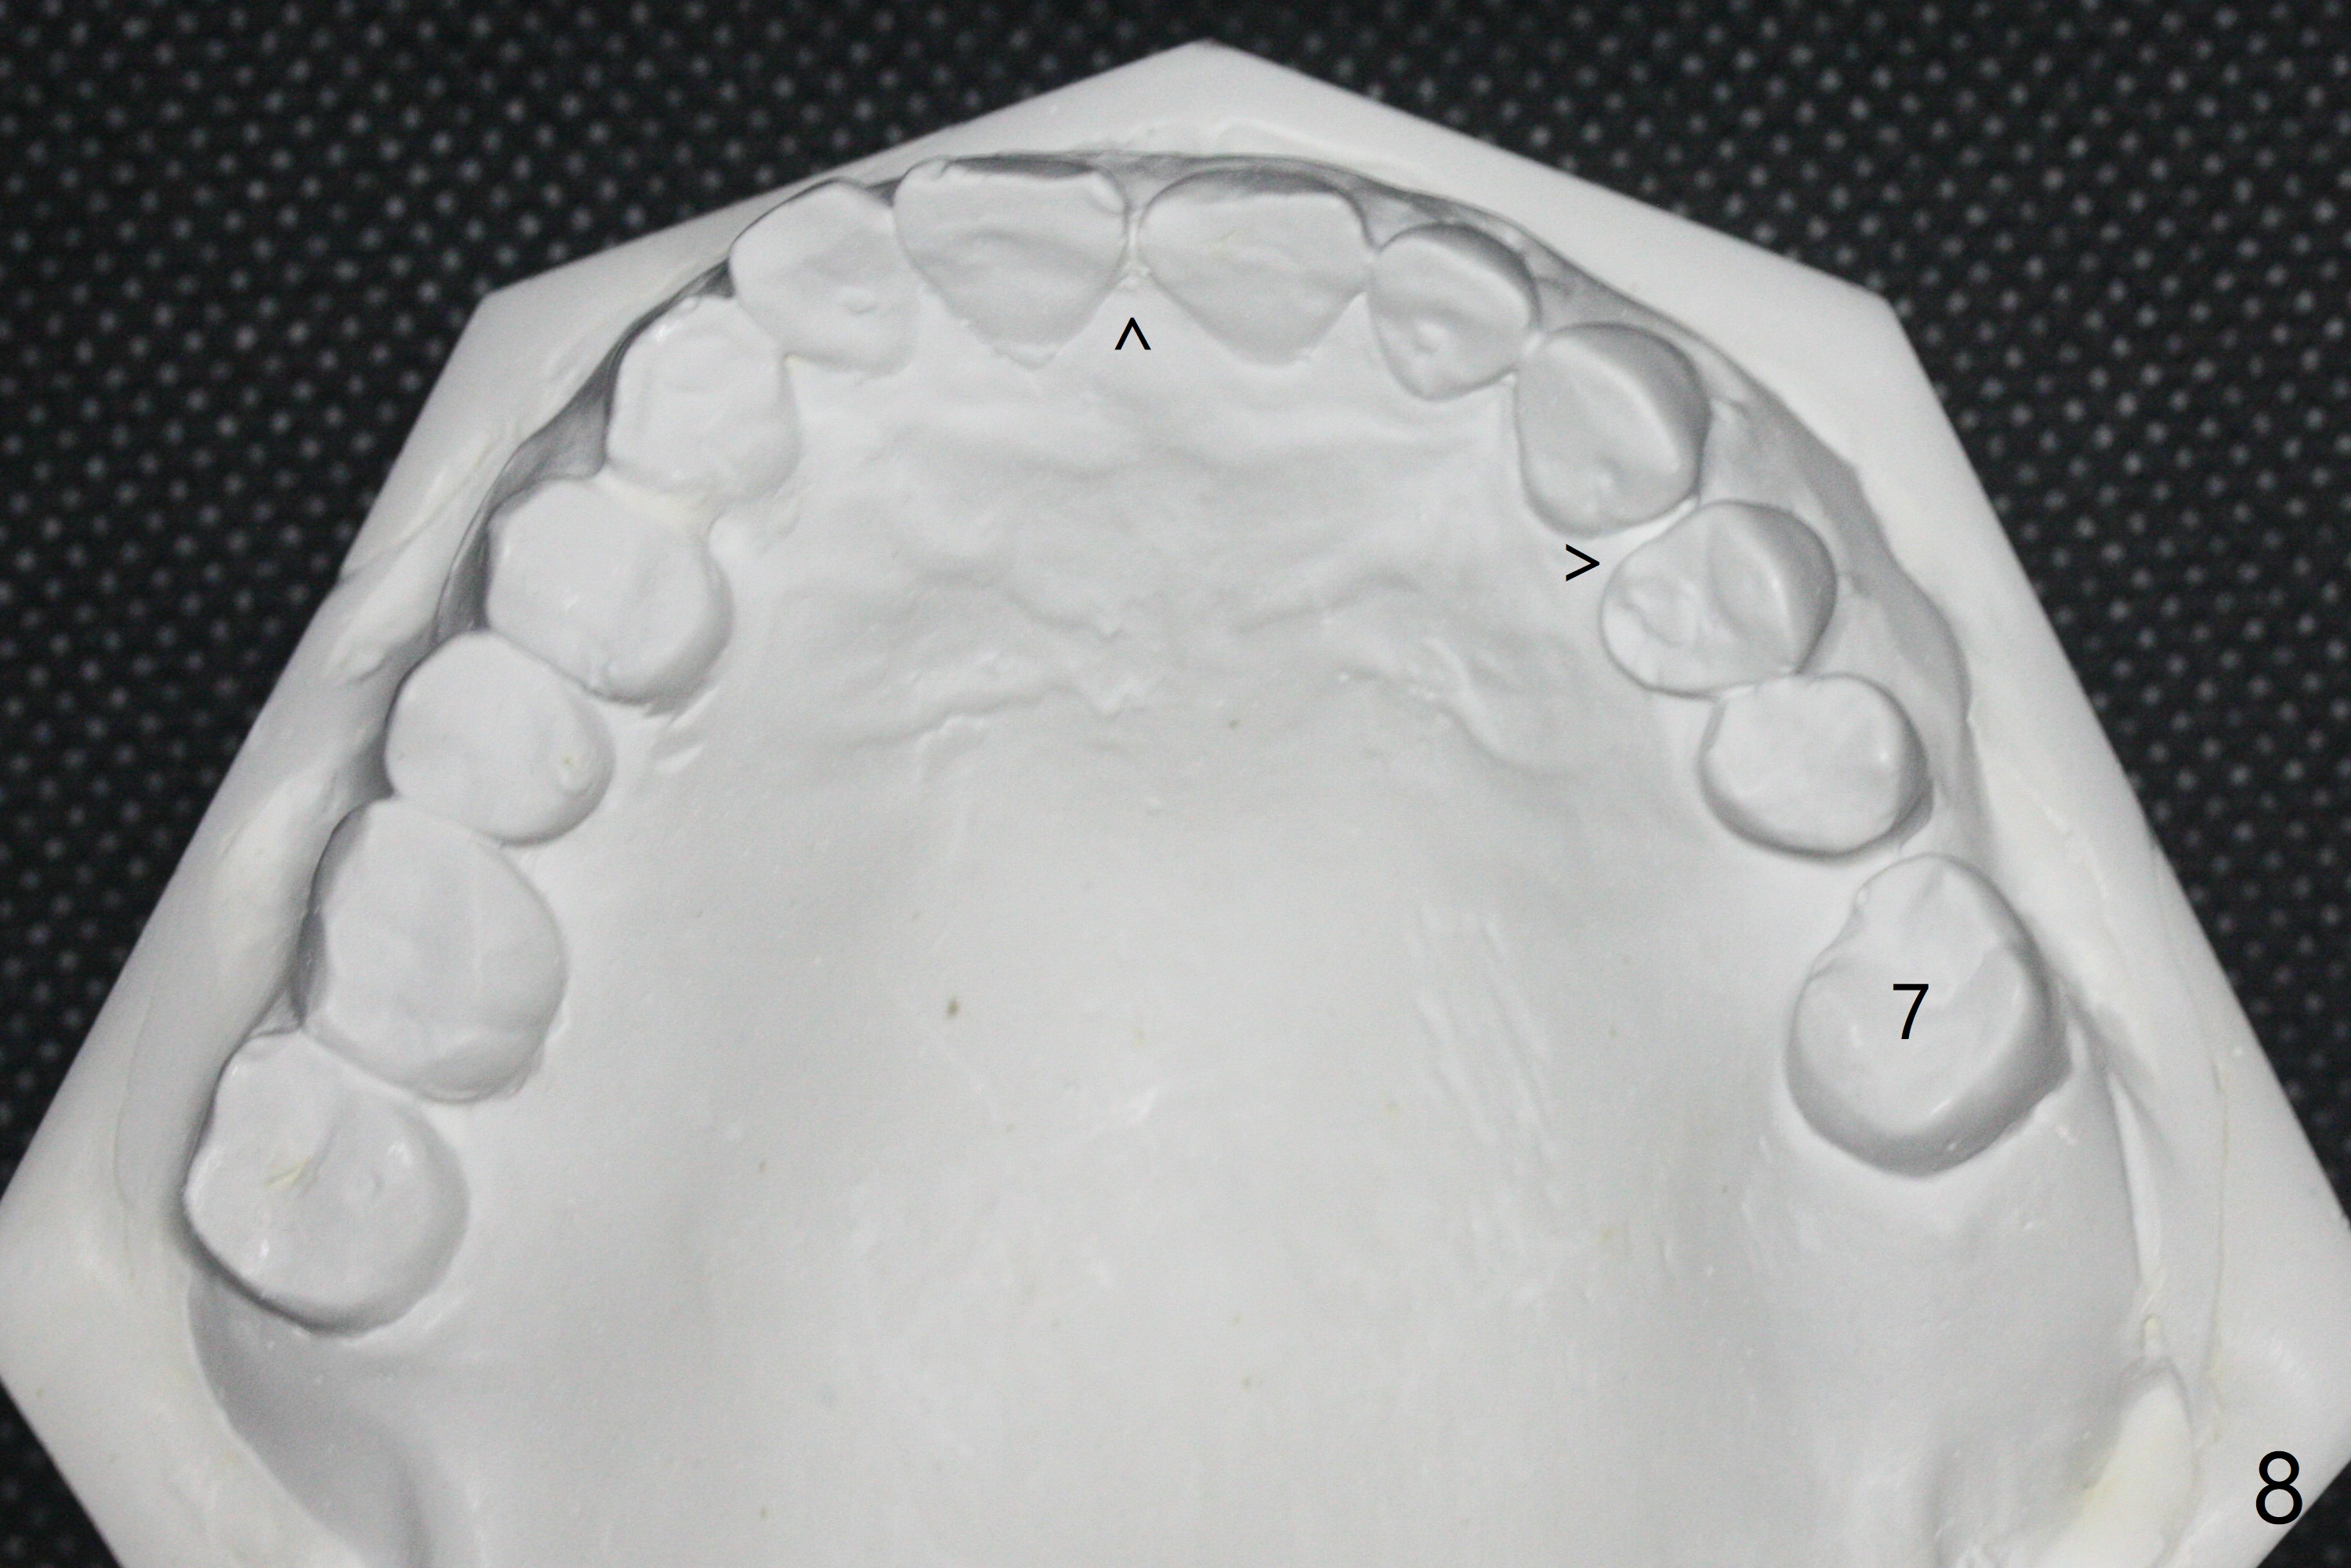

A 54-year-old man returns to office for UL7 upright 6 months post UR5 implant crown cementation (Fig.5,6). The ultimate purpose is to place implants at UL6 and LL 7. The latter will reduce severe occlusal wear especially in the lower anterior teeth (Fig.3,4). To solve the diastema between UR3 and 4 (Fig.1), the bracket at UR3 is placed in the height of contour (Fig.1 insert, Fig.4). Arch wire sequence may automatically close the diastema (Fig.1 insert arrows). In addition to tilting of UL7 (Fig.7), there are diastemata between U1s and UL3 and 4 (Fig.8,9 arrowheads). The patient is not tolerating orthodontic treatment well and requesting finishing the treatment early. We are considering mesializing UL7 instead of upright by placing a mini-implant between UL4 and 5 (Fig.10). There will be less interference of the roots of UL7 with the crown of the impacted UL8. There appears more space for a 1.6x8 mm mini-implant between UL4 and 5 (Fig.11) and UL 3 and 4 (Fig.12). Finally a mini implant is placed distal to UL7.